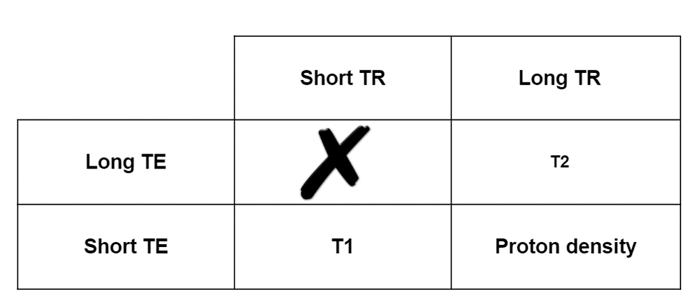

Contrast, in MRI, can be described as the ratio of the magnetization of two tissues. In the simplest terms, contrast is most often referred to by the predominate weighting. T1 weighting, T2 weighting or PD weighting. NOTE that the short TR and Long TE results in a useless image.